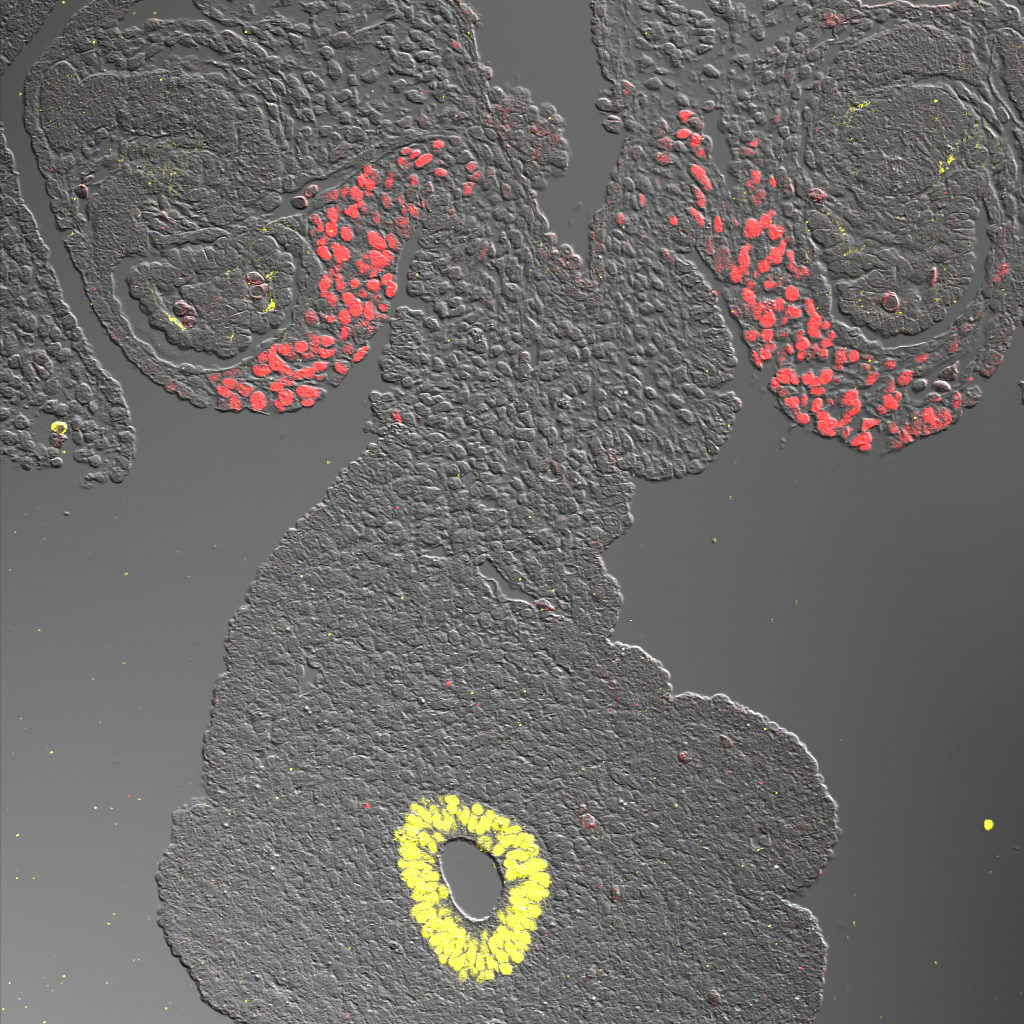

Jennifer Richer, Lyndsey Crump, and Nicole Spoelstra — University of Colorado, Aurora, Colo.

Breast cancer stained with a multiplex panel that we developed to stain for multiple hormone receptors on the same section. Here we see ER in red, AR in white, GR in green, Ki67 in Yellow, cytokeratin on tumor cells and cleaved caspase 3 in pink.